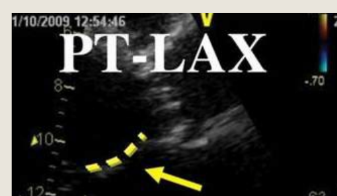

This is best evaluated in what view

In diastole (right), the intra-aortic pressure

forces the aortic valve leaflet to close, but

the unsupported right coronary cusp is

pushed down into the left ventricular

outflow tract away from the opposed

coronary cusp, resulting in regurgitation

This is best evaluated in PLAX

what is this showing

Doming of the anterior leaflet

Chronic AR significant compensatory are what and seen in which view with what

Significant compensatory LV dilation and

increased sphericity of the LV are seen in the

apical four-chamber view with chronic severe

AR